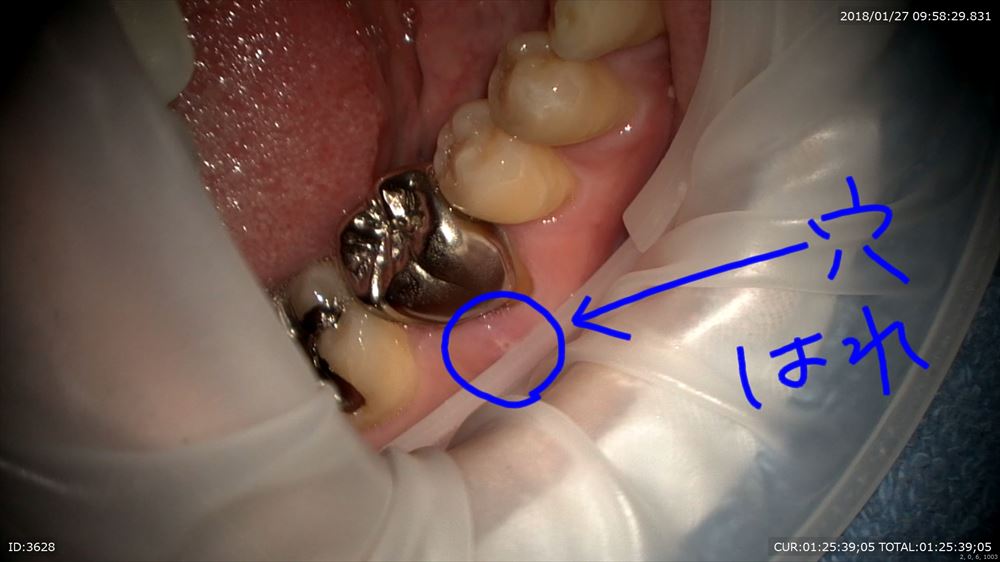

この潰瘍が消えない。違和感で来院

歯科ドックで根尖性歯周炎と診断